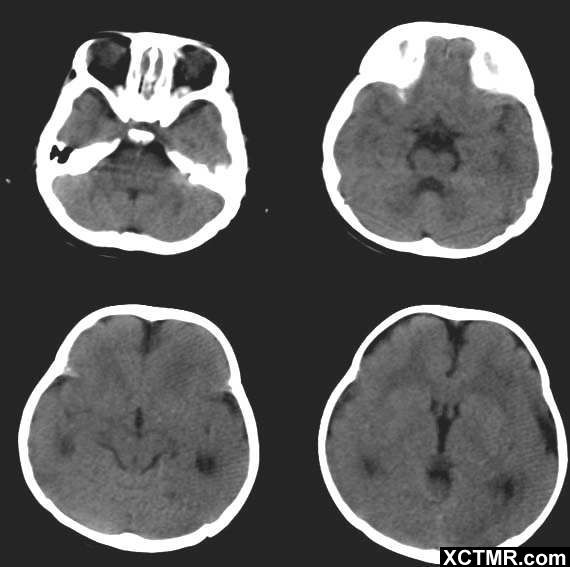

巨脑回的CT表现为:显示大脑半球皮质明显增厚,脑白质减少,脑沟变深多发生在额顶叶附近的蛛网膜下腔增宽病侧脑室扩大

除了巨脑回畸形,胼胝体发育不良外,患儿应还有侧脑室扩大畸形,因三角区及枕角周围白质明显减少,且无明显低密度改变而不支持PVL和肾上腺白质营养不良。 本畸形无特殊疗法以保守治疗为主,加强日常的锻炼。

本病以受累大脑半球弥漫性肥大为特点,并伴有一侧脑室扩张和中线结构移位,小脑和脑干亦可受累。病理示病变侧为无脑回或多小脑回改变,皮质增厚且皮质层结构紊乱。与健侧相比,患侧的神经元数目下降,胶质细胞数目上升。